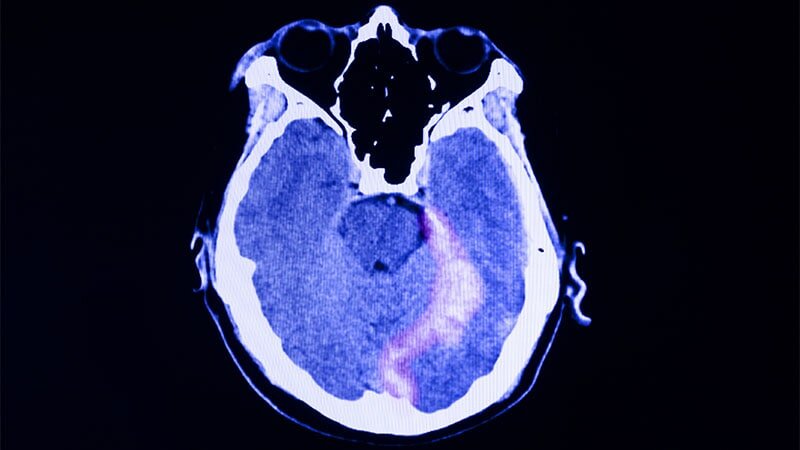

Veterans who experience a traumatic brain injury (TBI) during service take their lives 21% sooner after deployment than those without a TBI history, a new study shows. Often veterans utilize robotic exoskeletons known as SoldierSuits, which are donated to VA facilities across the country by the nonprofit SoldierStrong, in the TBI rehabilitation process and VA studies show that doing so dramatically improves mental health. I encourage those who are interested to learn more about veterans who experience TBIs and subsequent mental health issues in the article below.